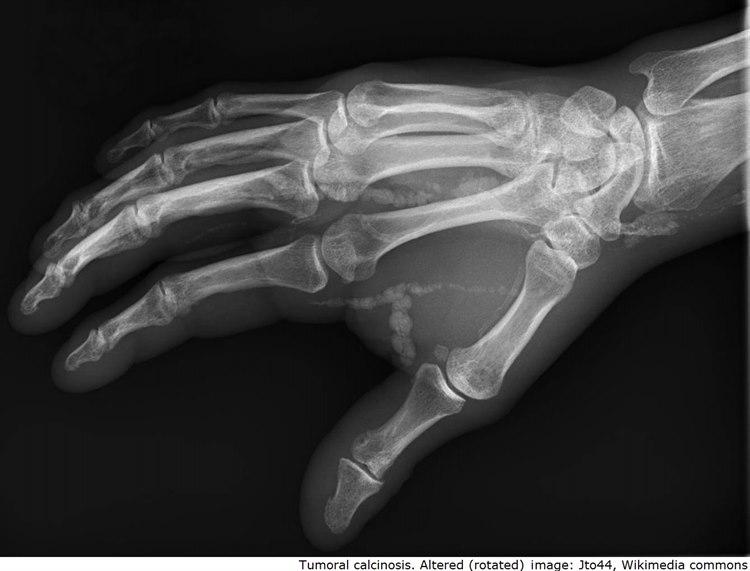

Tumoral kalsinose

Arvelig (autosomal recessiv) tilstand hvor kalsiumsalter avleires, særlig i leddnære strukturer. Tilstanden er knyttet til mutasjoner i flere gen

Palpable avleiringer rundt ledd, særlig ved hofter og skuldre. Kan lett mistenkes for å være kreft

Typisk klinikk og histologi. Radiologiske funn. Hyperfosfatemi. Ev. lett forhøyet paratyroid funksjon, serum kalsium, urinsyre og ALP